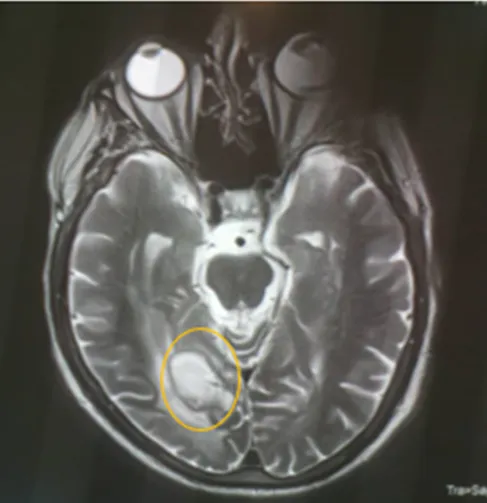

• En vista de compromiso Neurológico se solicita Resonancia Magnética Cerebral donde se evidencia:

Conclusiones del estudio Rx

En el presente estudio se observan múltiples imágenes quísticas de neurocisticercosis, de diferentes tamaños y en diferentes fases, vesicular, nodular y calcificadas, siendo la de gran tamaño la de localización parieto occipital derecha, con importante edema perilesional que genera efecto de masa desplazando estructuras y comprimiendo ventrículos.

En vistas de hallazgo de estudio de neuroimagen, es valorado por el ser servicio de neurología, quienes concuerdan que dichas lesiones son características de Neurocisticercosis, en sus diferentes etapas, siendo la de mayor tamaño de localización parieto occipital derecha en fase calcificada pero con importante edema perilesional.